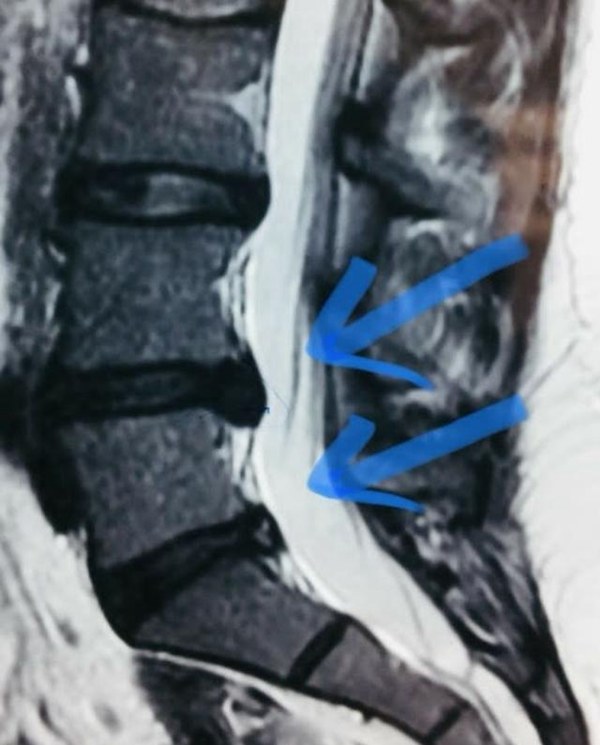

◎ 腰椎间盘突出症是一种腰椎间盘的退行性改变,由于纤维环的蜕变,破裂,导致髓核突出,继而压迫,刺激脊髓和神经根,最终出现下肢的神经压迫症状。/ 网络图片

“轻一点的情况,腰轻轻一动就不舒服,整体身体都感觉硬邦邦的,难以动弹;如果情况严重的,即便稍微一咳嗽,或者大小便稍一用力,腰部乃至整条腿都像电针扎样的疼痛感便接踵而来。”南方医科大学第三附属医院脊柱外科二区主任医师吴毅向39深呼吸形容,以腰椎间盘突出为例,它本质上就是一种神经性疼痛,这种对神经赤裸裸的压迫,严重时就像把自己的身上某一根筋用力扯出来,然后拿把刀使劲刮。

◎ 通过影像可见明显的腰椎间盘突出。/ 知乎